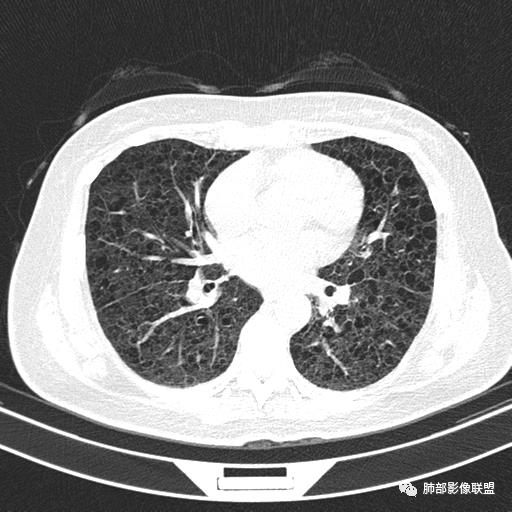

双肺弥漫囊腔,累及肋膈角,囊腔形态相对规则单一。

CT平扫示双肺弥漫分布大小不等囊状薄壁透光区,无内、中、外带分布差异,间质稍示增厚。拟LAM

中年女性育龄期妇女,咳嗽气喘,无吸烟史,有苯吸入史。影像:双肺弥漫均匀小囊腔,无明显分布优势,囊腔形态欠规则,壁薄,部分囊腔边缘血管征,伴双肺弥漫磨玻璃影,无结节,考虑lam,鉴别苯中毒肺损伤,囊腔多有分布优势,小叶中心分布为主,形态规整等

双肺弥漫大小不一薄壁含气囊腔,囊间肺组织正常,正常肺背景,肺尖肺底受累;青年女性,气喘,支持LAM

CT表现:双肺弥漫大小不等的薄壁囊腔,囊壁<2mm,外形规则,血管影多位于囊腔周围,囊腔之间肺组织正常,随着疾病进展到晚期,囊腔变大、增多,不可胜数,囊腔可融合成较大的囊,与肺气肿相似,形成间质性肺纤维化。部分病例可出现结节影。